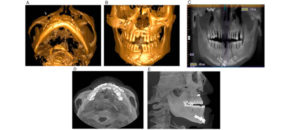

El «Área de contacto» es un término que se usa para denotar las alturas proximales del contorno de las superficies mesial y distal del diente.